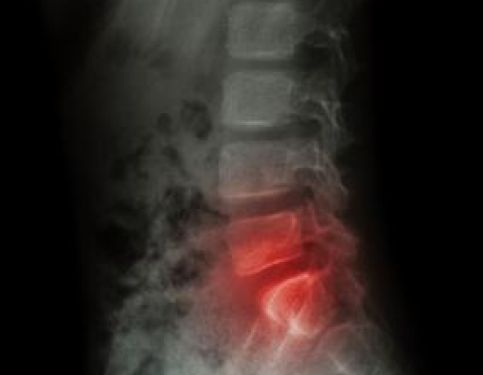

• Back Pain